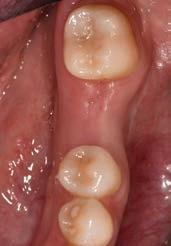

During the clinical oral examination, she didn’t exhibit any mucosal lesions, she presented an optimal level of oral hygiene but there were a lot of incongruous restorations and an apparently provisional restoration on tooth #25.

This element was not stimulated with the cold test and the radiographic image revealed an incomplete endodontic treatment (Figs. 1-2). The element seemed to present a suitable root length for a conservative restoration, but the apical position of the carious lesion and the proximity of the interdental bone ridge didn’t allow a correct rehabilitation with prosthetic crown, respecting the biological width.2

Figure 1: Initial situation. The patient reported generic pain in the second quadrant, where there was a restoration in temporary material on tooth number 25.